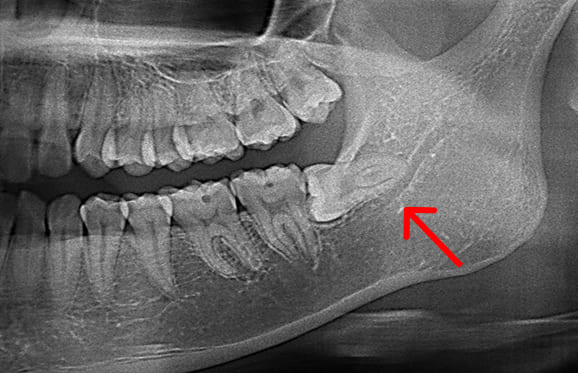

● 症例2

01 右上の頬側根に手用ファイルの破折

02 ファイル除去時

※若干の打診痛あり

03 最終の根充剤を充填

● 下の顎の親知らず抜歯 2回法

01 神経に近い位置に親知らずの根が存在

02 親知らずの頭の部分だけ抜歯

03 親知らずの根の部分が神経から離れる

下の顎の親知らずの抜歯では、神経の損傷リスクを考えて2回に分けて抜歯する場合があります。 また、麻酔が効きにくい場合にも、同様に2回に分けて抜歯します。